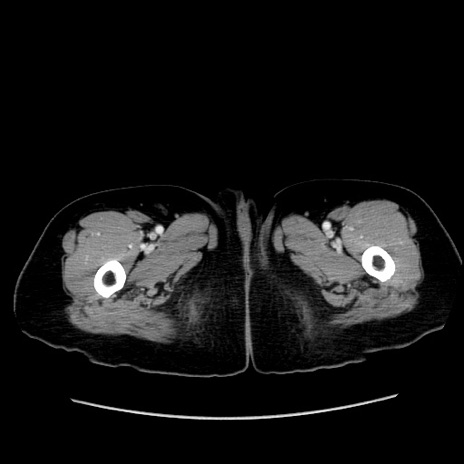

症例19(横断像)

【症例】80歳代女性

【主訴】下腹部痛

【現病歴】約8時間前より下腹部痛の出現あり、救急外来受診。

【既往歴】両側付属器切除

【身体所見】意識清明、下腹部正中に手術痕あり、その部位に一致して圧痛と反跳痛あり。腸蠕動音は亢進。

【データ】WBC 9300、CRP 0.15